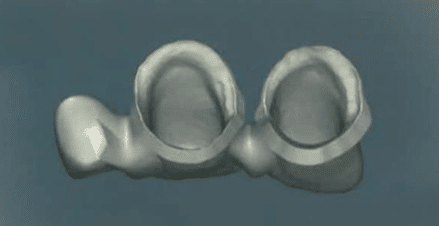

a) Pièces prothétiques :

Les moyens d’ancrage

Les moyens d’ancrage correspondent aux restaurations fixées sur les dents piliers.

Ils peuvent être :

Périphériques : couronnes.

Partiels : onlays.

Le choix du type d’ancrage dépend de l’occlusion du patient ainsi que des impératifs mécaniques, esthétiques et biologiques du cas clinique.

Le moyen d’ancrage est porté par une dent pilier, qui constitue le point d’appui.

Exemple : la dent représente le pilier, tandis que la couronne constitue le moyen d’ancrage.

La travée de bridge

La travée correspond à la portion du bridge qui remplace la ou les dents absentes.

On distingue :

Bridge à longue travée : édentement d’au moins deux dents.

Bridge à courte travée : édentement limité (une dent).

La travée est constituée d’un ou plusieurs éléments intermédiaires, appelés pontiques.

Les connecteurs

La liaison entre le pontique et les moyens d’ancrage est assurée par un connecteur.

Les matériaux

Les matériaux utilisés pour la réalisation des bridges d’usage sont principalement :

Les alliages métalliques.

Les céramiques.

b) Formes cliniques des bridges :

On distingue différentes formes de bridges en fonction de la topographie des piliers et des éléments intermédiaires (pontiques) :

Bridge "traditionnel"

- Fréquemment réalisé lorsque les piliers se situent de part et d’autre de l’édentement.

- Peut être :

Monolithique : d’un seul tenant.

En deux parties : désolidarisées, reliées par un système de connexion (glissière, taquet, etc.).

Exemple clinique :

Couronne périphérique sur la dent 7.

Dent 6 en pontique.

Préparation partielle sur la dent 5, servant de taquet.

Dans ce cas, la fixation n’est assurée qu’au niveau de la dent 7 et n’est pas optimale